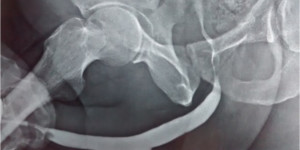

X-ray studies, Ascending urethrogram.

-

This test involves placing a fine catheter into the urethral opening

and injecting contrast media .The narrowed segment and the length of

narrowed segment can be visualized.